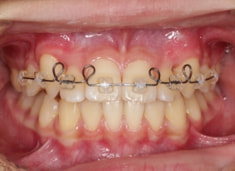

治療開始時

検査時のレントゲン分析では、上下顎の関係は、上顎の劣成長があり下顎前突傾向という値がでておりましたが、前歯ジャンプ後はフェイスマスクの効果もあり、上下顎の関係は正常化しています。

上顎が若干優位になっていますので、今後の下顎の成長のための貯金になっているくらいです。